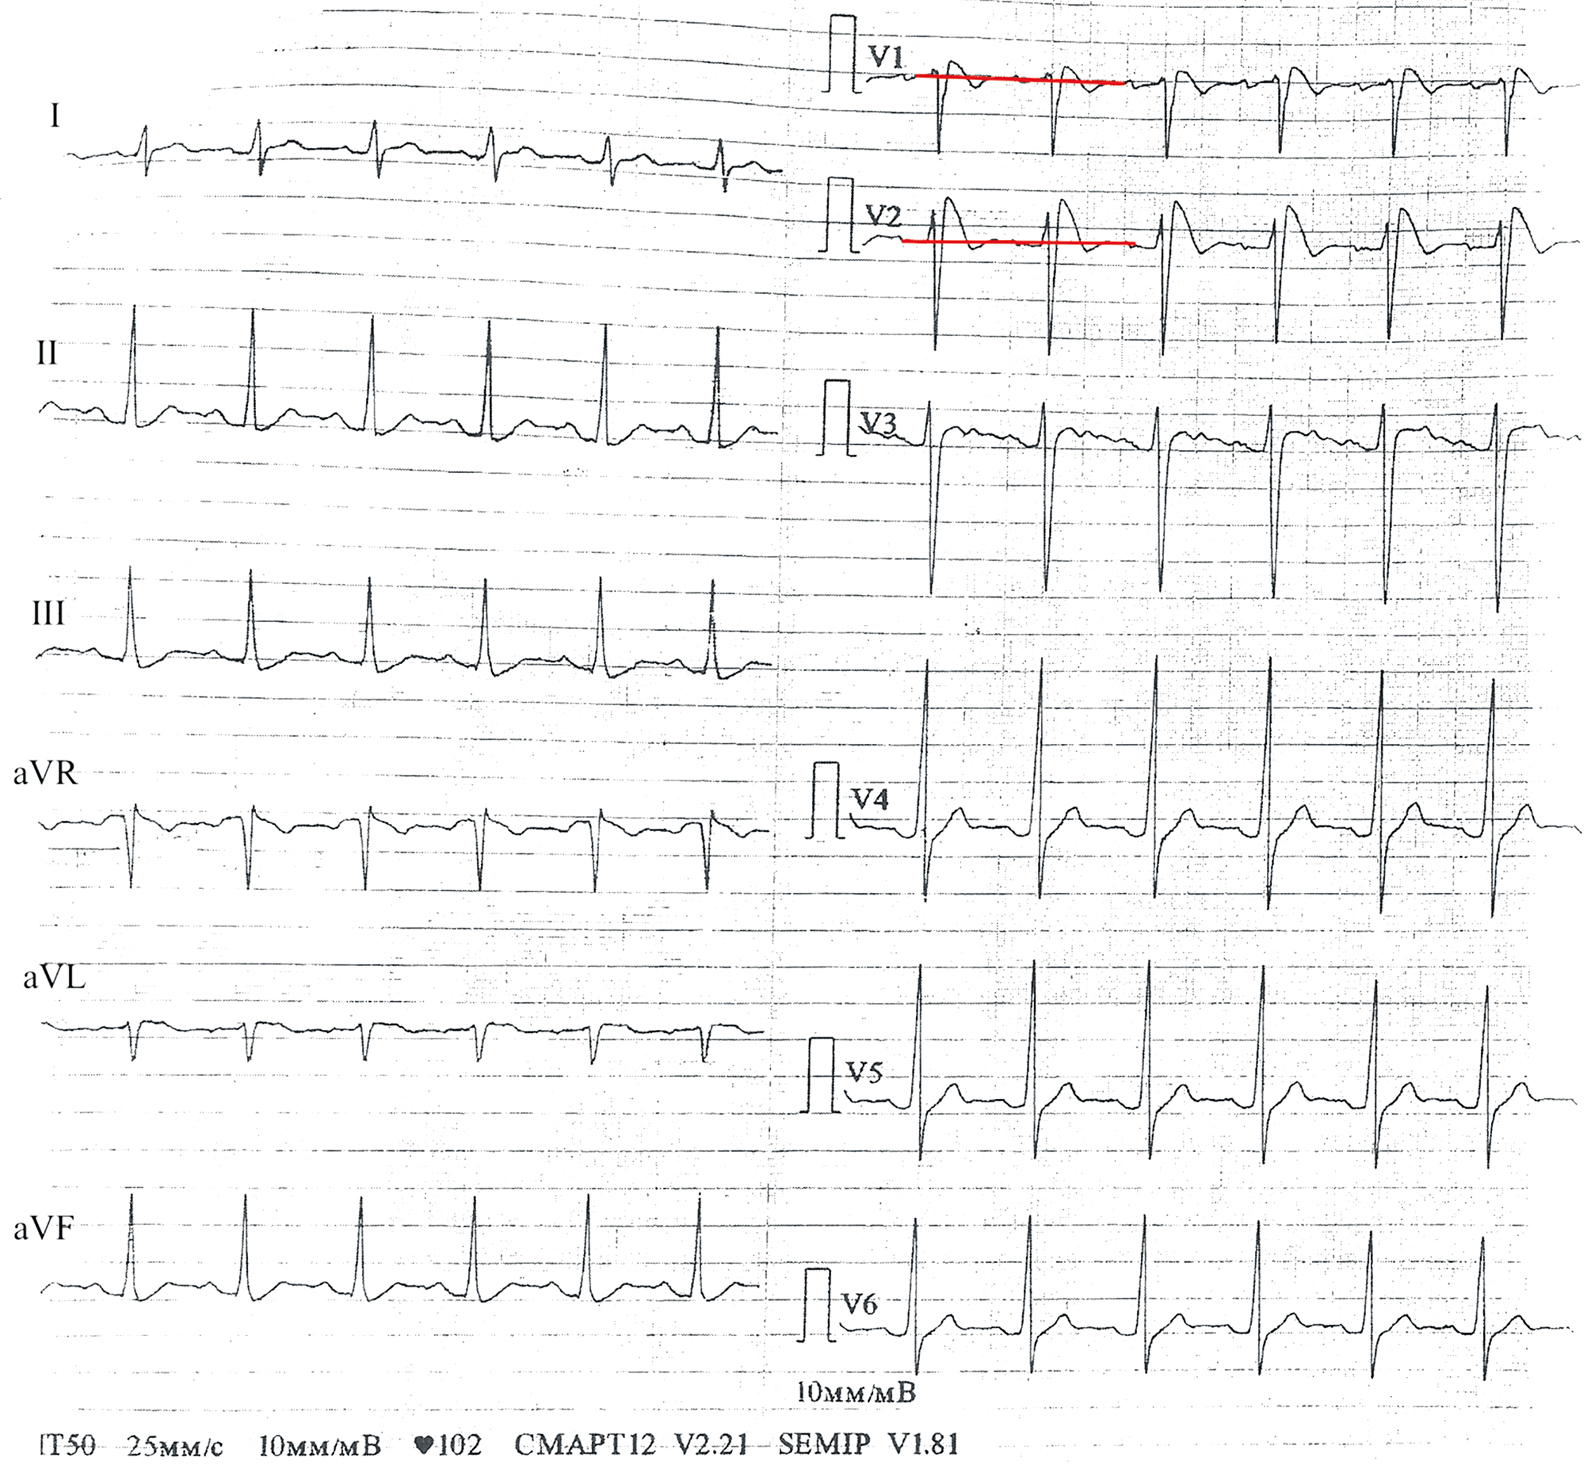

Patient 732 (female, 55 years old, no family history of SCD) who was admitted to the intensive care unit with cardiac arrest had a recorded VF and was subsequently implanted with an ICD. ECG showed a Brugada type 1 pattern (Fig. 4). Genotyping revealed a p.Asp1739Val substitution in the SCN10A gene encoding a neuronal sodium channel (Nav1.8), which has been associated with Brugada syndrome in recent whole-genome association studies. Phenotypic similarities have been demonstrated between patients with a SCN10A gene variant and SCN5A gene variants, including family history, presence of syncope, and spontaneous ECG pattern [16].

Fig. 4. 12-lead ECG of patient 732 with Brugada pattern type 1 (“coved”), showing a “vaulted” ST elevation of more than 2 mm in V1–V2, followed by a negative T-wave